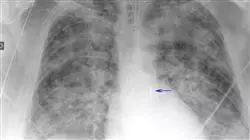

La gestione del paziente coronarico con sindrome coronarica acuta in terapia intensiva è una competenza fondamentale che deve essere acquisita dagli operatori sanitari dell'area cardiologica. Per questo è necessario avere una solida e aggiornata specializzazione accademica in materia, come quella offerta dal Corso Universitario in Gestione del Paziente Critico affetto da Sindrome Coronarica Acuta in Terapia Intensiva di TECH. In questo corso viene approfondita l'importanza di diagnosticare accuratamente il profilo di evento coronarico acuto del paziente. L'identificazione precoce dei segni e dei sintomi clinici è essenziale per stabilire il trattamento appropriato ed evitare gravi complicazioni. Pertanto, imparerai a eseguire una valutazione dettagliata del paziente, che comprende l'anamnesi, l'esame fisico e i test complementari, come l'elettrocardiogramma, gli esami del sangue e la radiografia del torace. Un altro aspetto fondamentale del corso è la capacità di stabilire la strategia di trattamento appropriata per il tipo di evento coronarico di cui soffre il paziente. Sarai in grado di valutare i rischi e i benefici di ogni trattamento e di prendere decisioni informate in base alle esigenze del singolo paziente.